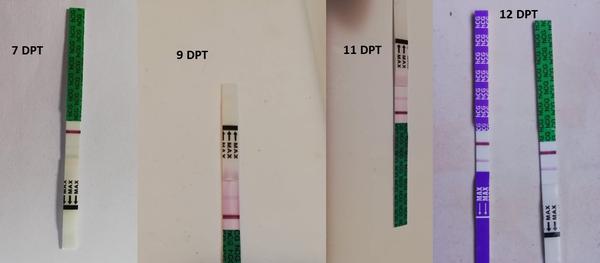

@lenja227 nie nie, nemusi. ani na 10 deň nemusí byť. všetko záleží aj od toho, ktorý deň po KET nastalo uhniezdenie. mne napríklad doktorka povedala, že to môže byť až do 7 dní od KET, a potom jasne, že na 6 deň nebude žiadna čiarka. mne sa na tom tvojom teste tam zdá, že tam je a to ja som väčšinou fakt že slepá, všetci píšu že vidia a ja nevidím nič.

Baby ste fakt zlaté, takáto podpora je super vec a dáva mi to nádej 🙏🙏 dám dva dni pauzu do stredy od testovania, a potom skúsim testom Baby Top Test taky fialový tiež prúžkový.